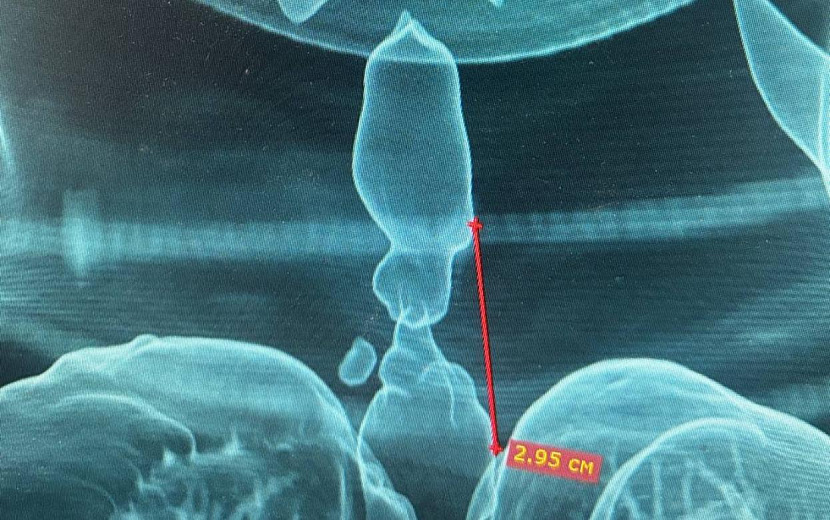

Женщина стала жертвой тяжелого ДТП, долгое время провела на аппарате искусственной вентиляции легких. В дальнейшем у нее появилась выраженная одышка и характерный шум при дыхании. В ходе бронхоскопии и компьютерной томографии врачи выявили рубцовое сужение – стеноз трахеи. Далее была создана трехмерная модель дыхательных путей пациентки.

Протяженность стеноза составила 2,95 см, а минимальный просвет трахеи – 5 мм. Жизнь пациентки находилась в опасности. Торакальные хирурги Максим Мясников и Ильяс Гумеров провели срочную операцию – циркулярную резекцию трахеи. Пораженный участок был удален, а целостность дыхательных путей восстановлена за счет формирования межтрахеального анастомоза.